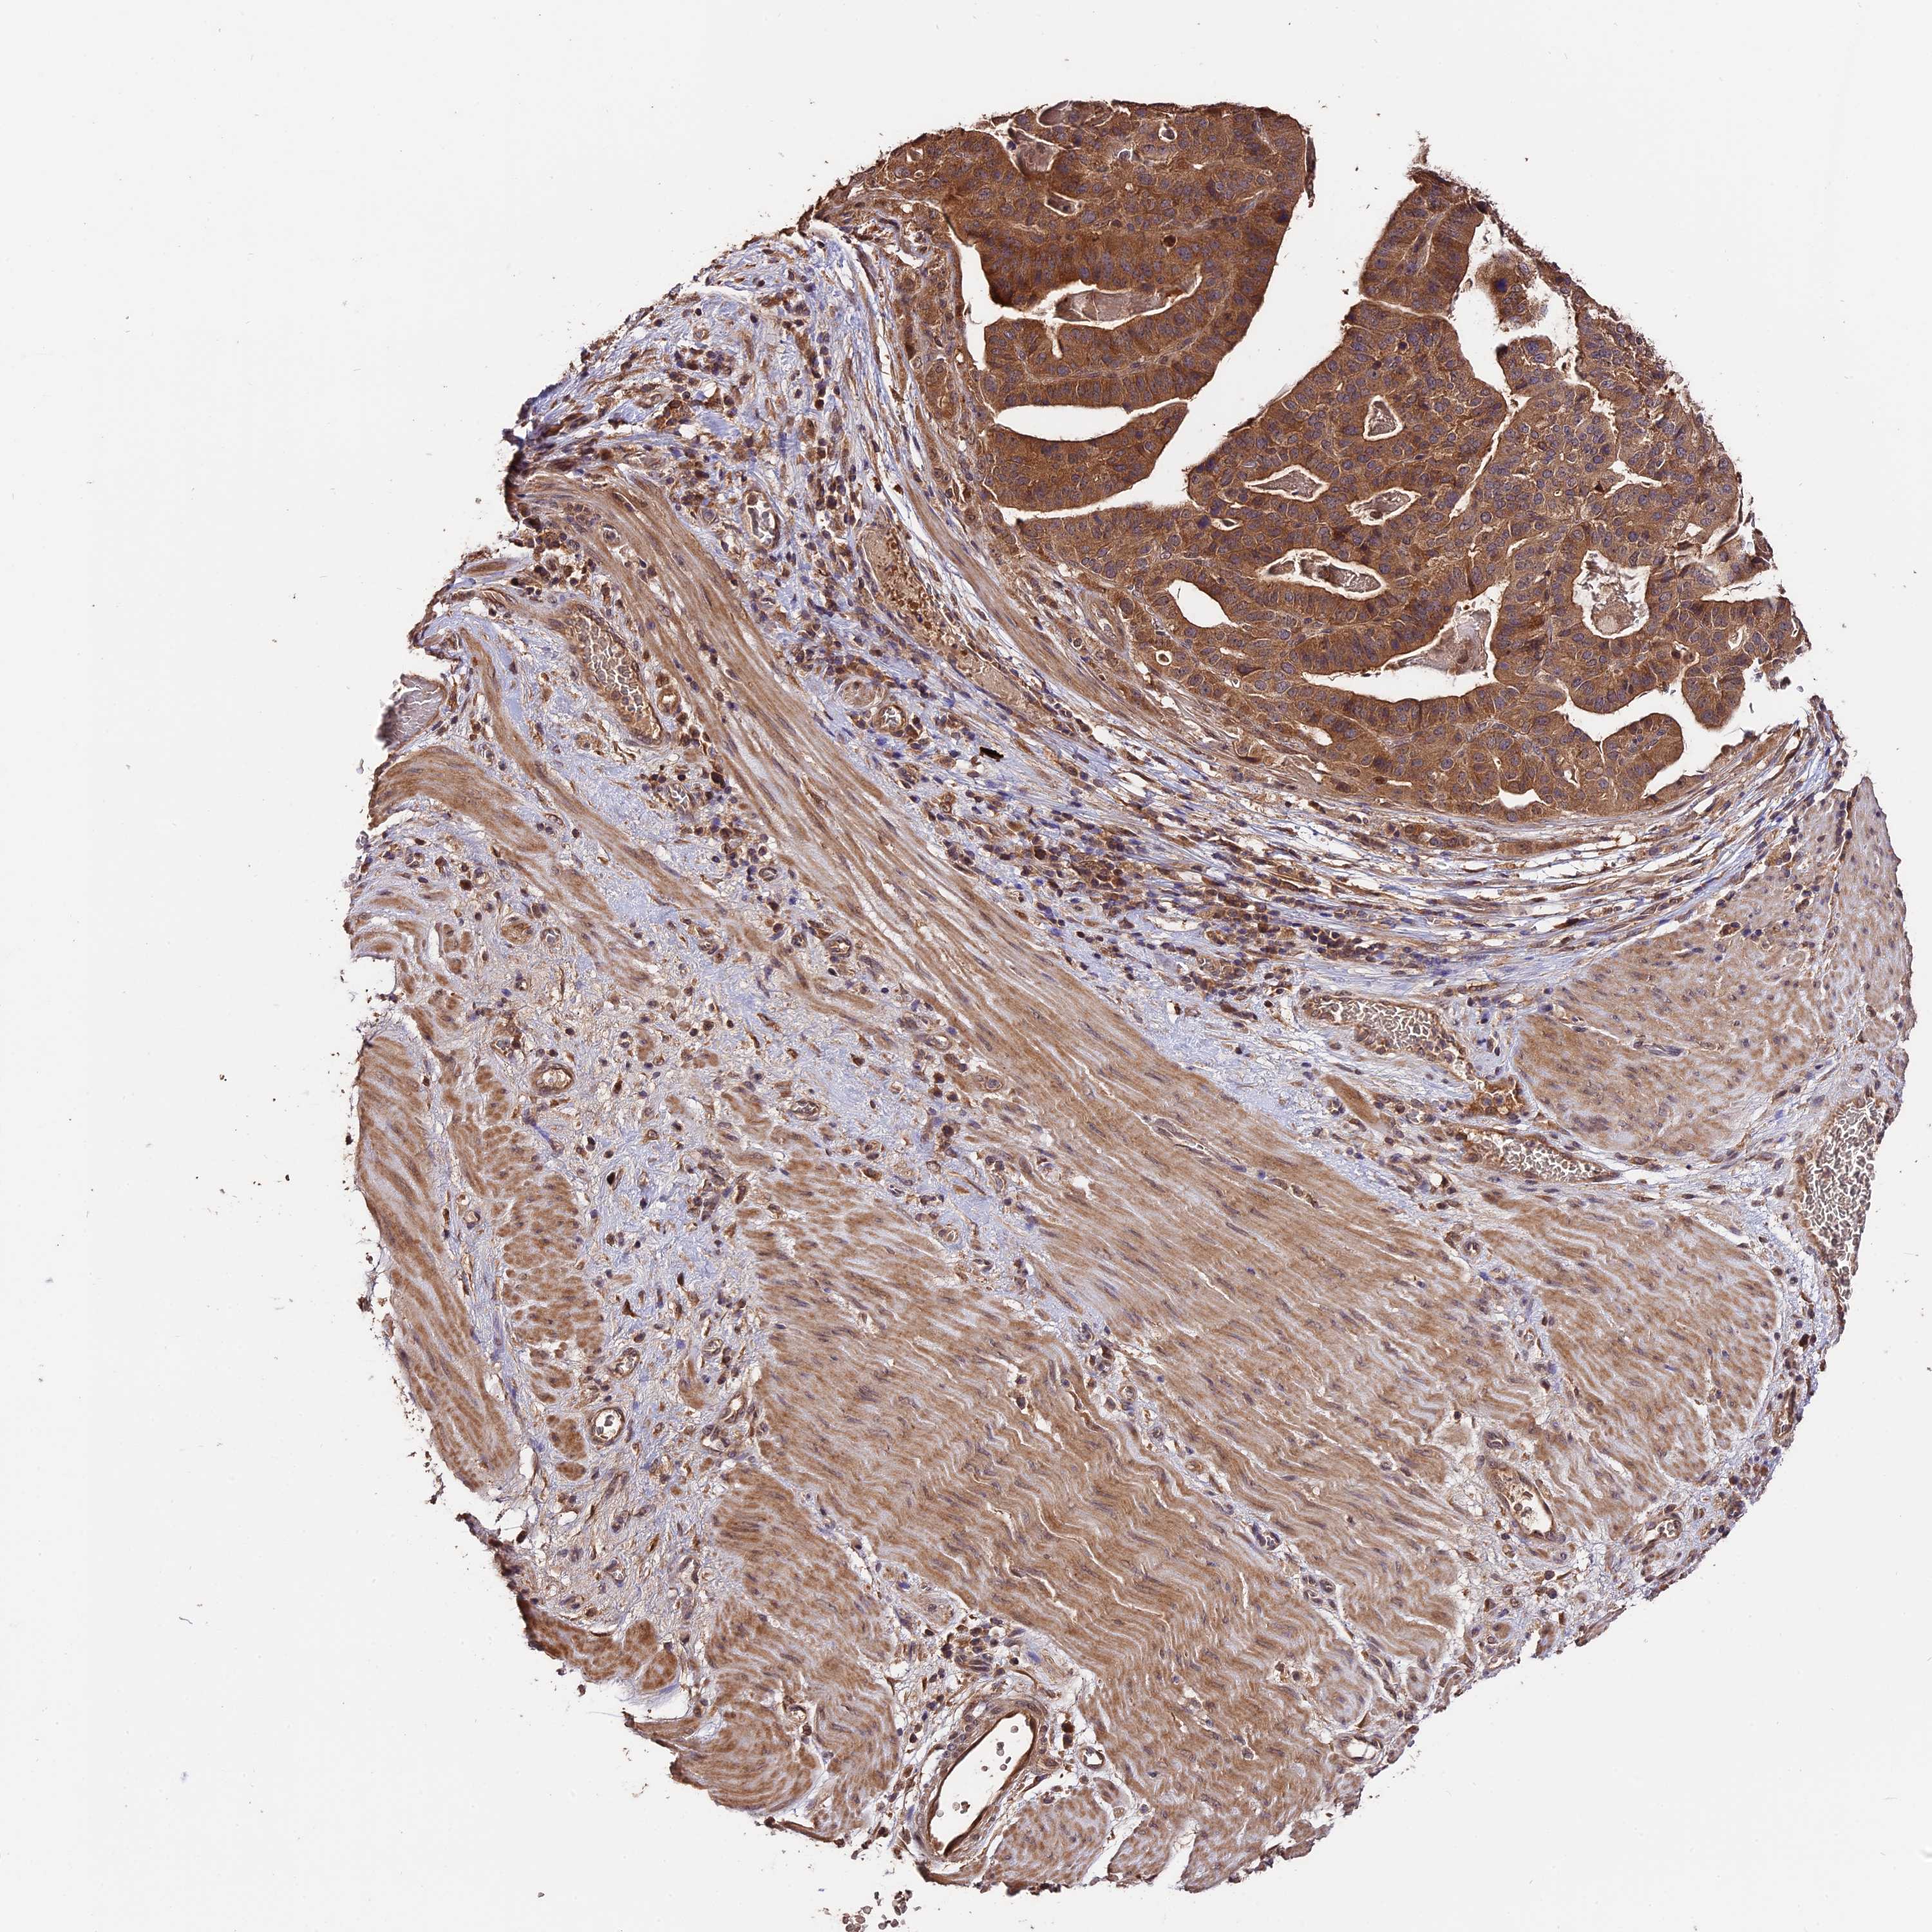

STOMACH CANCER - Protein expressioni

A mouse-over function shows sample information and annotation data. Click on an image to view it in a full screen mode. Samples can be filtered based on level of antibody staining by selecting one or several of the following categories: high, medium, low and not detected. The assay and annotation is described here.

Note that samples used for immunohistochemistry by the Human Protein Atlas do not correspond to samples in the TCGA dataset.

Antibody stainingi

Antibody staining in the annotated cell types in the current human tissue is reported as not detected, low, medium, or high, based on conventional immunohistochemistry profiling in selected tissues. This score is based on the combination of the staining intensity and fraction of stained cells.

Each image is clickable and will lead to virtual microscopy that enables deeper exploration of all samples and also displays staining intensity scores, fraction scores and subcellular localization as well as patient and tissue information for each sample.

Antibody HPA041130

Antibody HPA041380

Staining

High

Medium

Low

Not detected

Intensity

Strong

Moderate

Weak

Negative

Quantity

>75%

75%-25%

<25%

None

Location

Nuclear

Cytoplasmic/membranous

Cytoplasmic/membranous,nuclear

Adenocarcinoma, NOS